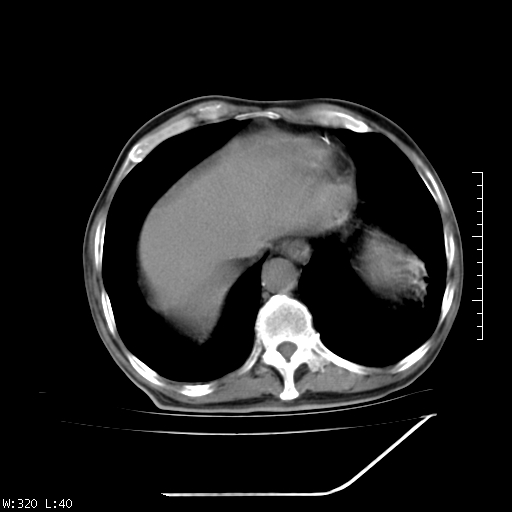

标题: CT23994:男、72、咳嗽、气短两月余,近来消瘦。 [打印本页]

标题: CT23994:男、72、咳嗽、气短两月余,近来消瘦。

右上肺实变,与胸膜关系密切,右肺容积缩小,隆突下淋巴结增大,考虑1 肺结核 2 肺癌

右上肺大片状密度增高影,与胸膜关系密切,内见低密度透亮影,胸膜下可见三角形不张影,左下肺沿支气管走形结节影,纵膈内淋巴结显示。考虑结核并疤痕性不张可能性大,建议穿刺活检,排除肺泡癌。